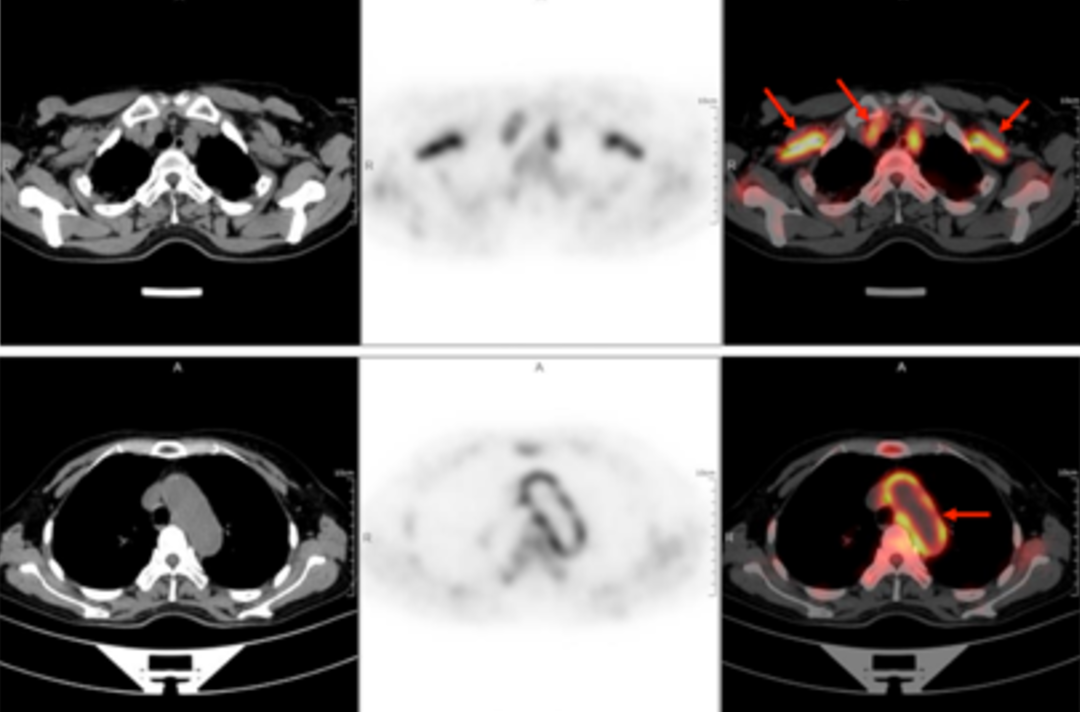

A 58-year-old women went to the hospital for intermittent fever for more than 40 days. Her highest body temperature was 38.9℃. Other symptoms included fatigue and shoulder joint pain which were especially acute in the afternoon and at night without cold, chills, sputum, hemoptysis, chest pain, chest tightness and shortness of breath. After two weeks of intravenous administration of "cephalosporin antibiotics" there was no improvement, and intermittent fever continued. The outpatient clinics noted the patient had "fever of unknown origin." There were no obvious diagnostic features upon physical examination. The results of a routine blood test were as follows: erythrocyte sedimentation rate in the first hour: 72mm; high-sensitivity C-reactive protein: 204. 20mg/l. Then, the patient had a whole-body F-FDG PET-CT examination to find the cause of the fever of unknown origin.

In the PET/CT images, wall thickening with increased glucose metabolism occurred in several parts of the body (bilateral internal carotid artery, common carotid artery, brachiocephalic trunk, bilateral subclavian and axillary arteries, thoracic aorta, abdominal aorta, bilateral common iliac artery, internal iliac artery, external iliac artery and femoral artery), which was considered to be caused by inflammatory changes. Combined with the patient's medical history, clinical symptoms, examination and imaging findings, she was diagnosed with T.A. After standardized anti-inflammation treatment, her body temperature dropped and her condition improved.